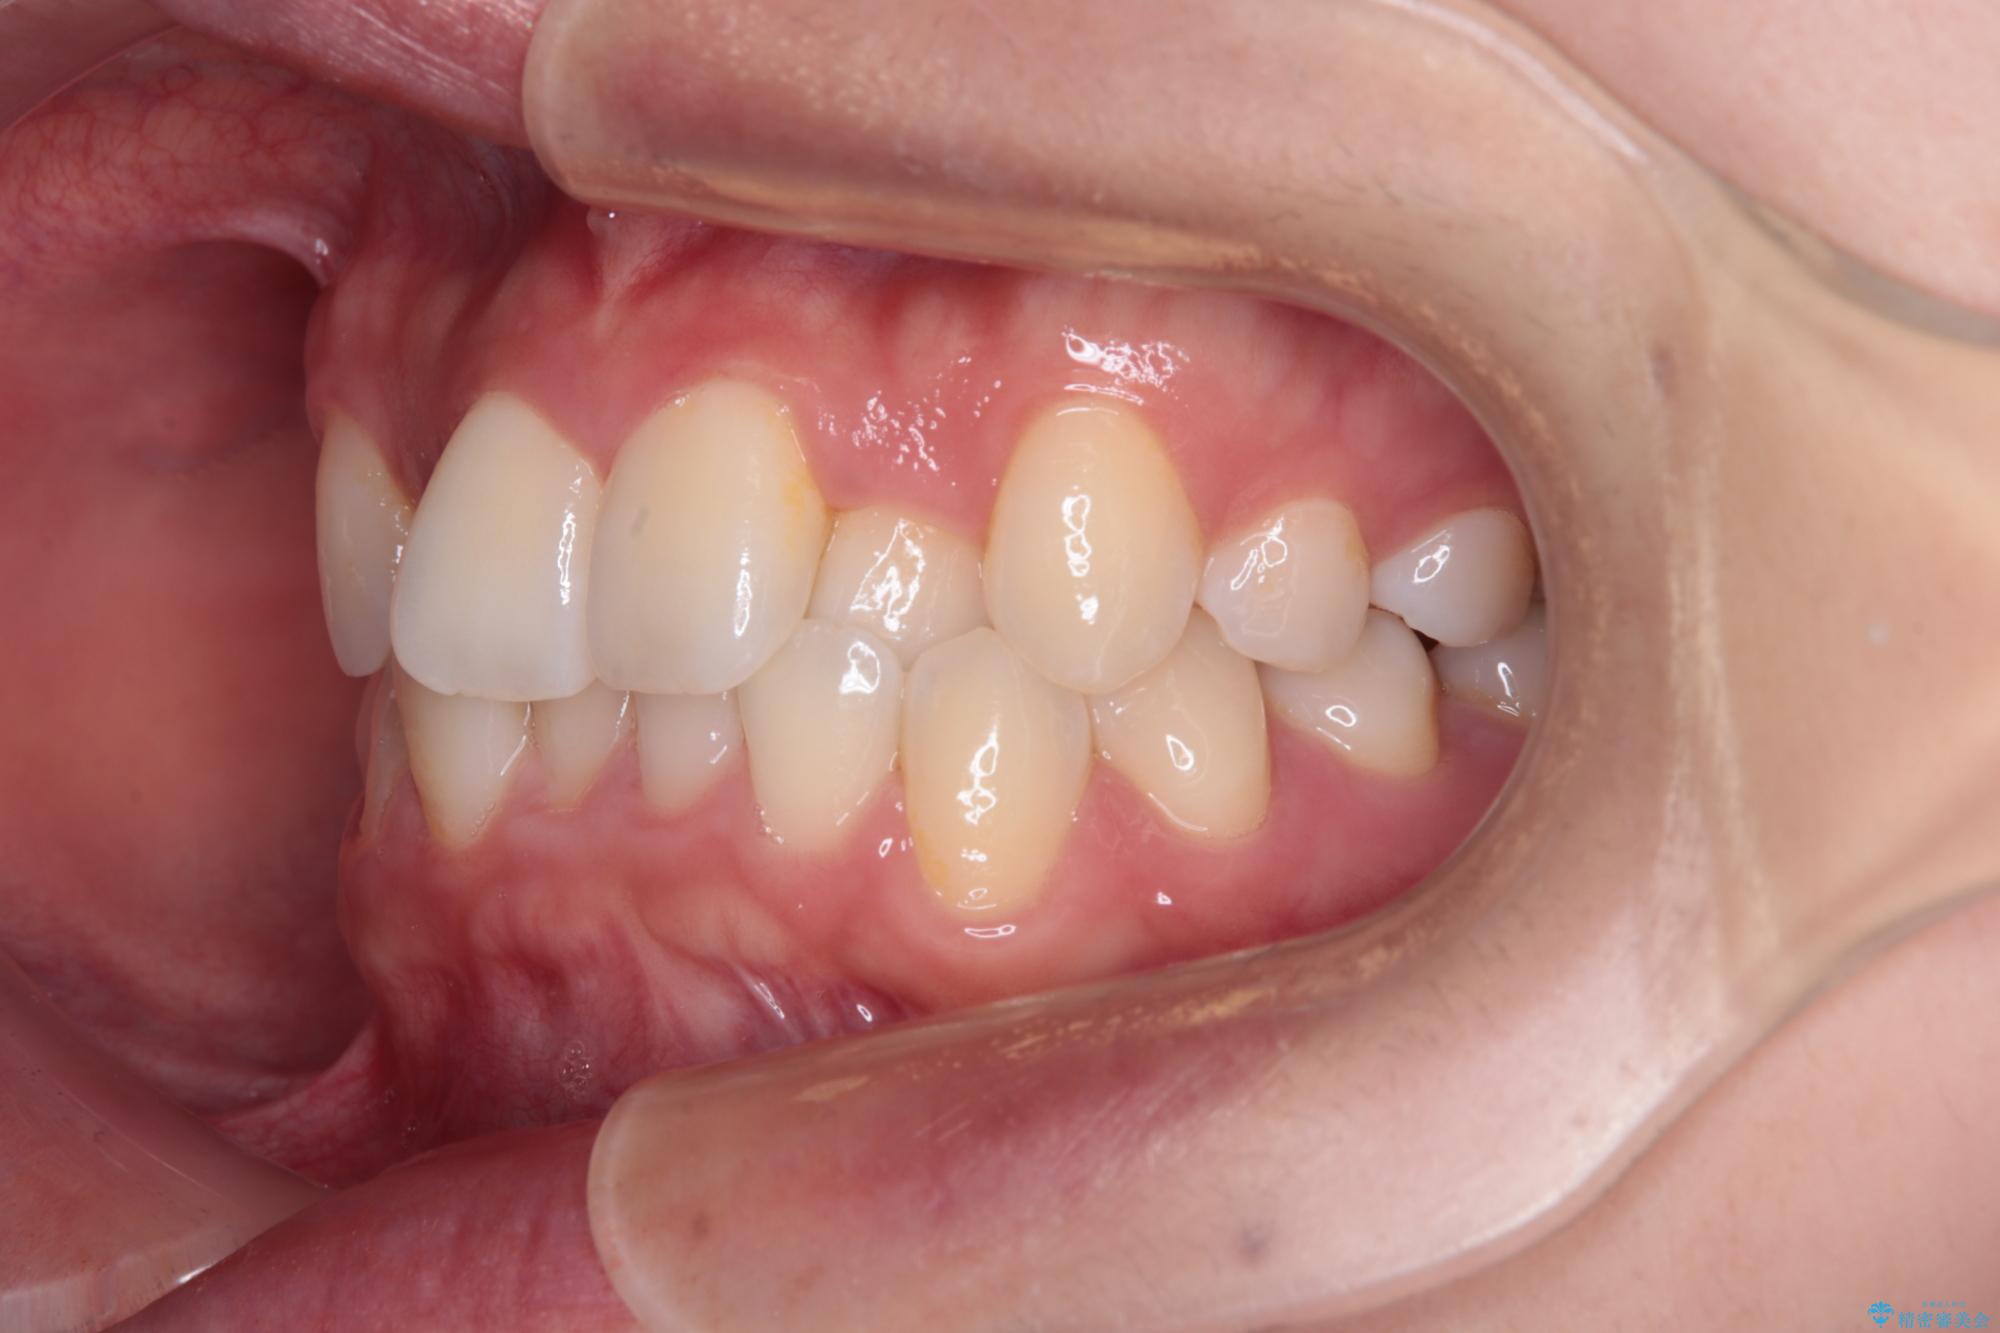

- 上顎前歯のクロスバイトを気にして来院された患者様です。

ワイヤー矯正でもマウスピース矯正でも対応可能でしたが、マウスピースによる自己管理に一切の自信がないとのことで、ワイヤー装置にて矯正治療を行うこととしました。

装置の外見を気にしていましたが、短期間で治療を終えることができるだろうと伝えると、安価であるメタルブラケットを選択されました。

想定通り、1年強で綺麗に仕上げることができました。